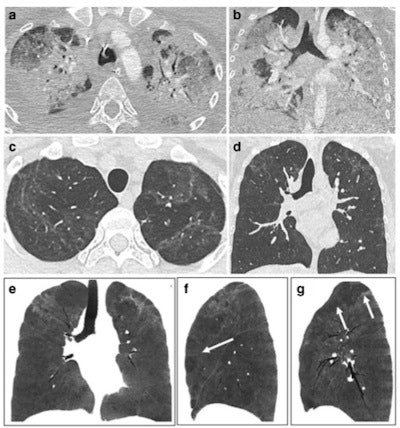

CT features at baseline, and one-year follow-up, in a 30-year-old woman who developed severe COVID-19 pneumonia (intubation, 40 days in intensive care unit). a,b: Baseline CT showing extensive ground glass opacities (GGOs) and consolidation. c–g: 1-year CT follow-up. Residual GGO, with a linear shape, is mainly seen in the upper lung, suggestive of organizing pneumonia at a late phase. There is no bronchial dilatation, signs of architectural distortion, or honeycombing, as confirmed by minimum intensity projections (minIP) (e, f, g). The sagittal minIP reformations (f, g) demonstrate plurilobular areas of decreased attenuation (arrows). This mosaic attenuation pattern might be due to either residual small airway disease or peripheral vascular obstruction. Decreased diffusing capacity (DLCO) at one year was 64%.The report devotes a section to the role of CT pulmonary angiography (CTPA) and dual-energy CT (DECT). DECT enables assessment of pulmonary perfusion and the detection of capillary microvascular thrombosis.